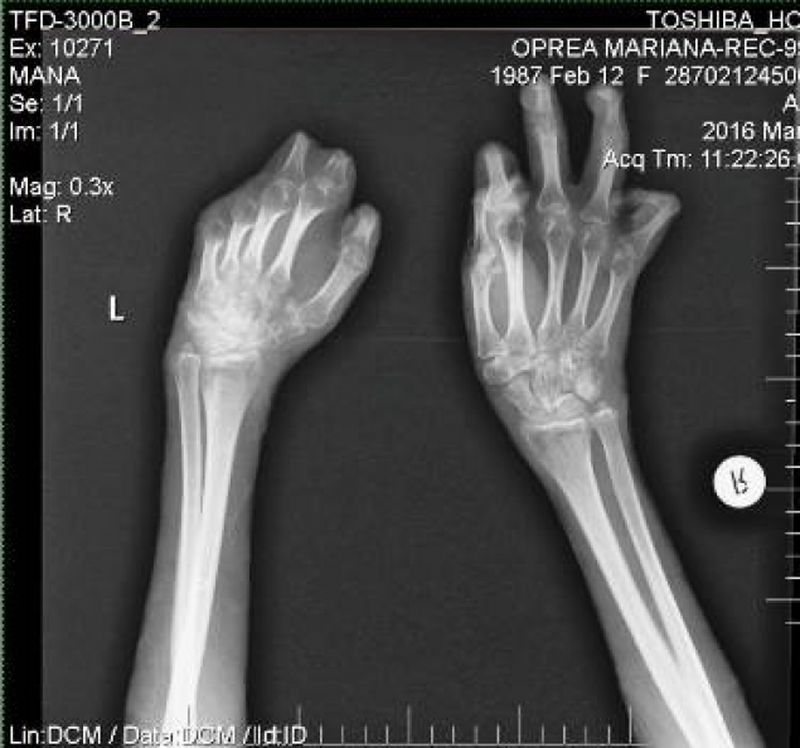

Mariana Oprea, poreclita Tedy de catre amici, trece printr-un adevarat cosmar dupa tragedia din Colectiv. Arsurile i-au afectat scalpul si bratele, iar o parte din degetele de la maini i-au fost amputate.

Mi-aş dori foarte mult să pot să am o proteză bionică pentru mâna stângă, care nu mai are niciun deget. Chiar dacă intervenţia va fi una grea şi vor trebui să îmi taie jumătate din palmă pentru a o integra, o proteză dintre cele de generaţie nouă poate prelua până la 95% din funcţiile normale ale mâinii. O proteza ajunge la 90.000 de euro”